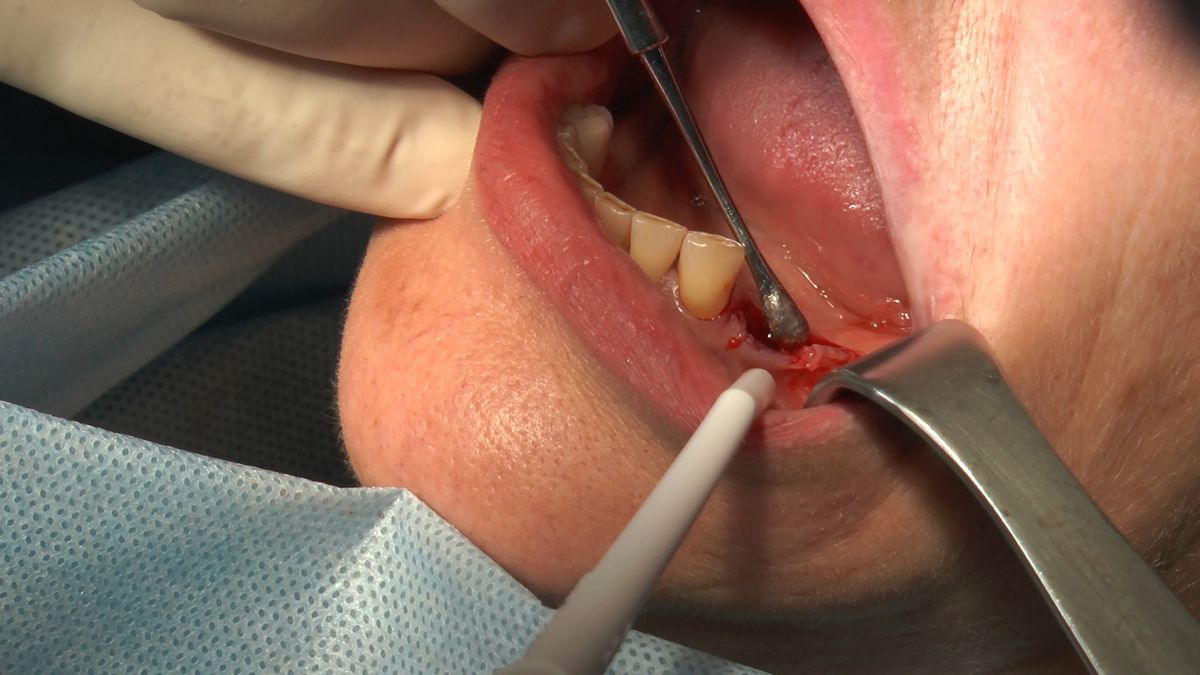

W ostatni weekend czerwca 2018 roku kursanci II Sezonu Preludium Implantologii odbyli piątą, finałową sesję, która w całości podporządkowana była praktyce. W ciągu dwóch dni zabiegowych Lekarze uczestniczący w szkoleniu przeprowadzili szereg zabiegów pod kierunkiem dr n.med. Violetty Szycik. Wszczepili 17 implantów oraz przeprowadzili ekstrakcje i zabiegi regeneracyjne kości. Zabiegi były wykonywane także w sedacji dożylnej z udziałem specjalisty anestezjologii i intensywnej terapii dr Jolanty Grzybowskiej. Preludium implantologii to nowy program edukacyjny dla adeptów implantologii stomatologicznej, którego celem jest wprowadzenie do implantologii poprzez pozyskanie wiedzy w szerokim zakresie i uwzględnieniem szczegółów mających decydujące znaczenie dla powodzenia leczenia implantologicznego. Ale tak jak wszystkie szkolenia w Instytucie Vivadental, w tym wiodące Practiculum Implantologii, zorientowane jest na praktyce i samodzielnym wykonywaniu zabiegów pod kierunkiem Mentora. To najlepsza edukacja w medycynie zabiegowej, a zarazem najlepszy start do implantologii.